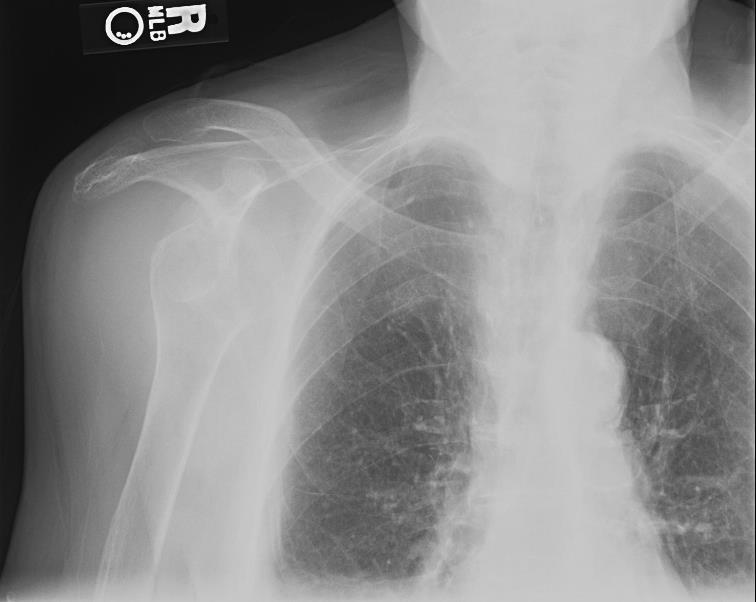

What is the presentation for a patient with anterior shoulder dislocation?

abducted and externally rotated

“squaring” of the shoulder: loss of rounded appearance (humeral head) and sharp prominence of the acromion

What is a Hill-Sachs lesion?

dent in the humeral head

compression chondral injury of the posterior superior humeral head following impaction against the glenoid